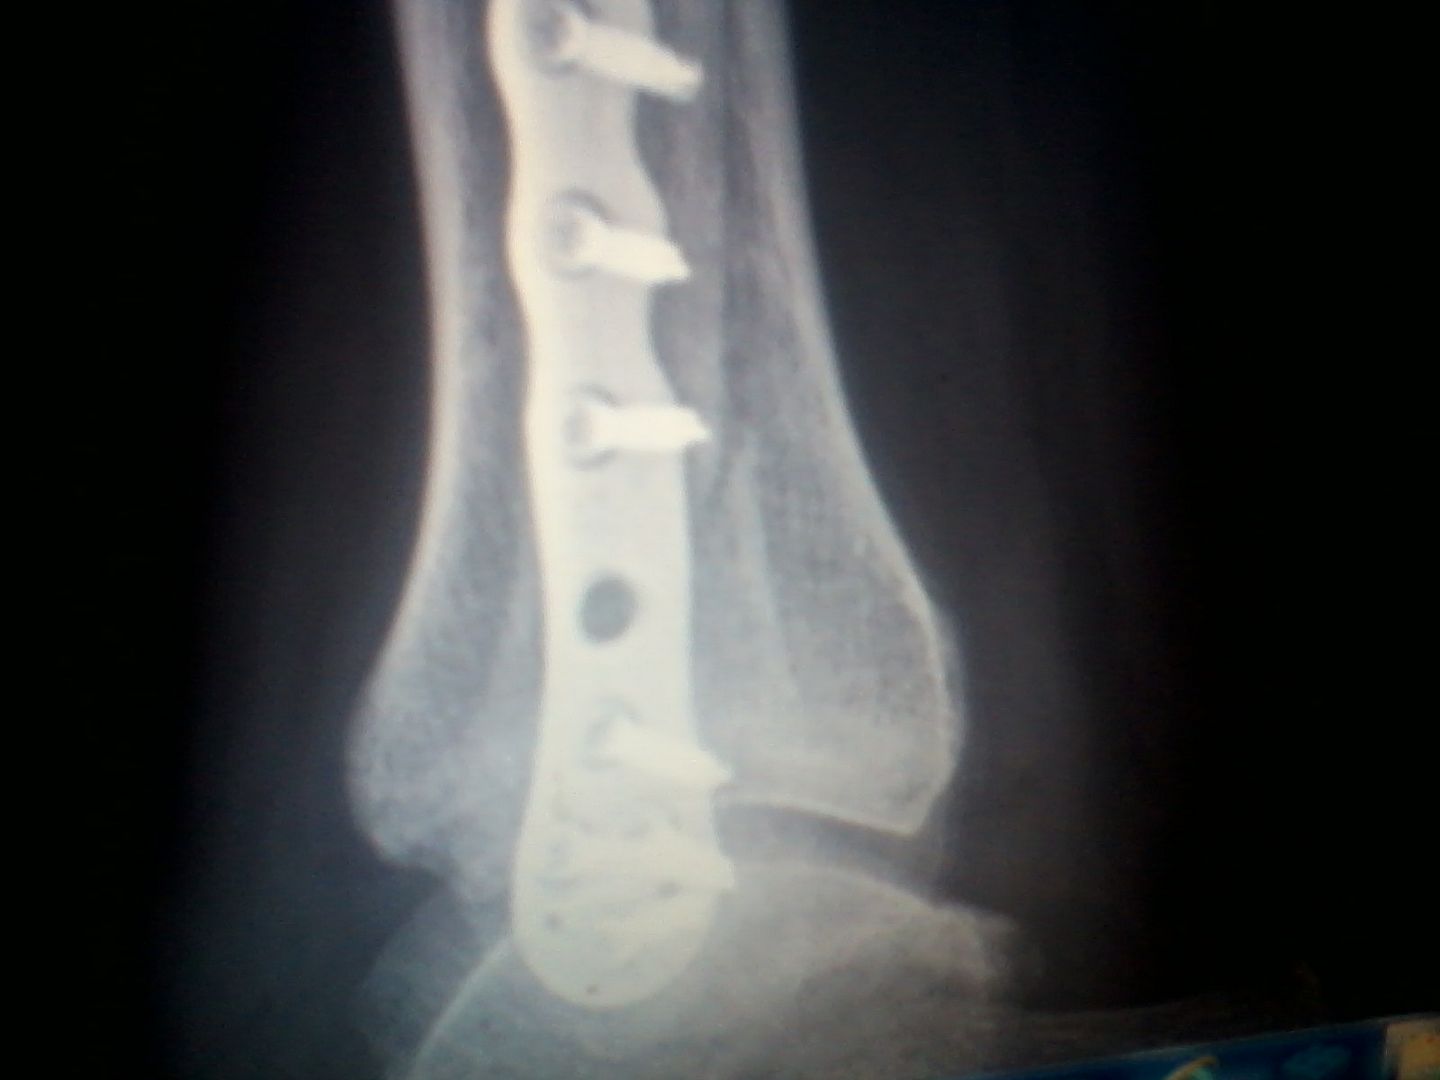

the latest xray pics youll see trhe hole in brace unhealing crack is between it and screw above it. more evident on frontal shot

this is ORIF surgery ( Open Reduction Internal Fixation) this also has some NSFW tones to it because it shows images during process. only difference between this procedure and mine was i didnt have a screw put UP thru the bone along with the plate. you can see the screw going thru the bone. up thru the middle of it. everything else is spot on. again this could have some NSFW or appetite lol

Calling ortho again today. THIS TIME  for left ankle tib fracture.bwell occured on 19th aug. you will see the vertical plane i.e it goes up/down or angles greater than 30deg from horizontal. had an ill be damned moment. ankle pain on left woke me up. had my dvd from hosp.   with reports and all since 12th august. pulled 19th up zoomed in. ill be damned there it is. now for some reason this happened on outside of distal tib. at fib mortise. however today noticing when i wrapped it either using provided lace up ankle brace it put pressure on the medial distal tib. and it hurt like help. ( and it fails / hits a positive) on tib/fib squeeze test. :/ and hurts WORSE to elevate. wtf lol. i know it wont be painless but was fine since almost day 1. until a few days ago. granted i wasnt 100% compliant as far as NWB but it was minimal. still am NWB (non weight bearing) on right ankle fib fracture distal. repaired using ORIF a titanium plate and screws. bone is not growing together but it can wait for now. the left concerns me. what sounds funny is the only way it feels remotely better is to stand up. :/ meh will update later on as soon as i know something